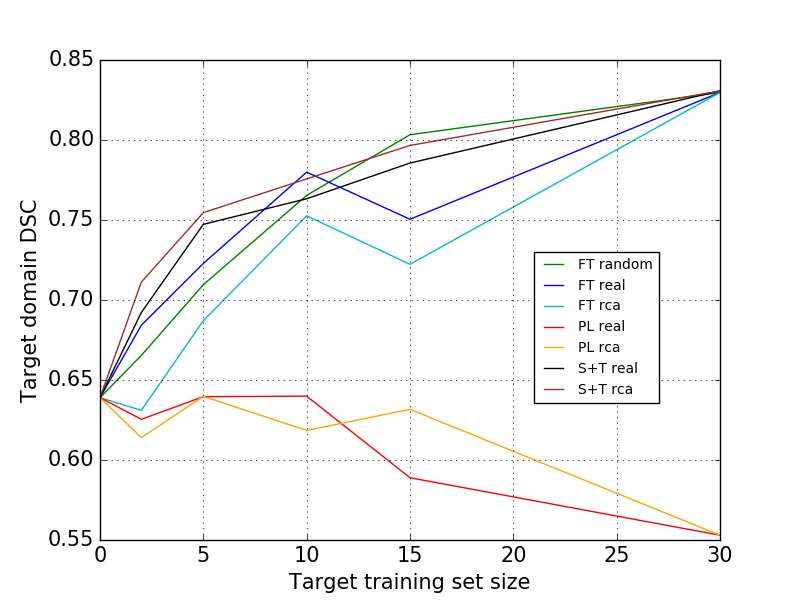

In Figure 2-2, we fine-tune the pre-trained network (from S), with -subjects selected by RCA. Fine-tuning requires less time than training from scratch. Here, we fine-tune with three different selections (random, real DSC, and RCA) at different set size (2, 5, 10, 15, and all of the T data). Table 3 shows the results when we fine-tune using all of the T data which is very similar (DSC: 0.830) to when we train from scratch (DSC: 0.831).

As we did in Section 3.1, we also combined best-5 and worst-5 in T domain to be annotated and incorporated in fine-tuning. This 10 combined subjects give much better accuracy than when we choose only the best-10 subjects (Table 3). Similarly, picking up the worst sample in increasing number, results in lower accuracy than the ’best 5 and worst 5’. Best-5 and worst-5 annotated samples with real selection shows the best results (DSC: 0.842), and RCA selection also gives similar results (DSC: 0.835). Additionally, this best-5 and worst-5 combination (real and RCA selection) performs better than when we use all of the annotated subjects from T (DSC: 0.830). Hence, we cut the cost of annotation by 67%, using only 10 selected subjects instead of 30 subjects and achieve a higher accuracy.

However, from Table 3, it is clear that using pseudo-labels cannot improve the segmentation performance on the target domain. Fine-tuning with all of the pseudo-labelled subjects in T gives the worst result amongst all. The noisy labels negatively impact the segmentation performance. Hence, training using pseudo-labels seems not suitable for domain adaptation in our application, since it assumes the baseline classifier to be of good quality, while by default it should be considered to be severely suboptimal.

Set size and subject selection are important in domain adaptation, where usually labels are not available in one of the domains. Thus, we explored whether it will be useful to select only the “valuable” subjects by RCA to be annotated. Pseudo-labels, which normally are used in semi-supervised learning and regularization, seem not to be useful in supervised DARCA. As observed in Figure 3 the performance drops as we increase the number of pseudo-labels in fine-tuning. Pseudo-labels will introduce more noise confusing the training of the networks and make them incapable to be applied to the new domain.